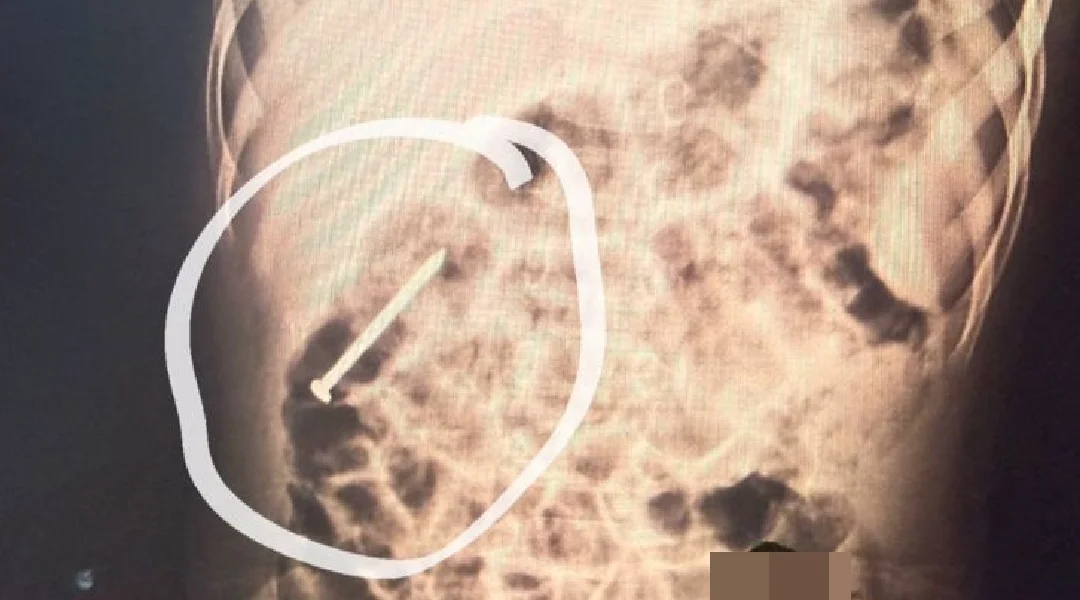

Um menino de dois anos, residente no município de Ipixuna, permanece internado no Hospital do Juruá após ingerir um prego há aproximadamente seis dias. Desde a admissão, a criança está sob observação da equipe médica da unidade.

Segundo os profissionais de saúde, o objeto metálico vem se deslocando pelo sistema digestivo de forma espontânea. Como medida preventiva, o paciente segue hospitalizado para acompanhamento contínuo, enquanto se aguarda que o material seja eliminado naturalmente, sem necessidade de procedimento invasivo.

Até o momento, o quadro clínico do menino é considerado estável. A equipe médica realiza exames periódicos e mantém vigilância constante para assegurar que não surjam complicações durante a evolução do caso.